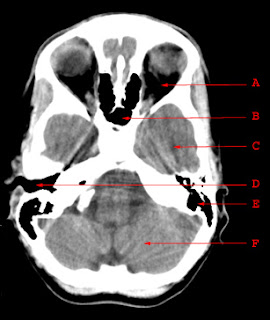

Normal Anatomy of CT brain at skull base

A. Orbit

B. Sphenoid Sinus

C. Temporal Lobe

D. External Auditory Canal

E. Mastoid Air Cells

F. Cerebellar Hemisphere